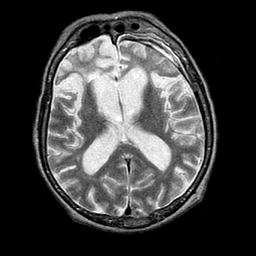

Pick's Disease, MR Study mr-t2 -- Slice #12

[Home][Help][Clinical] Slice 12